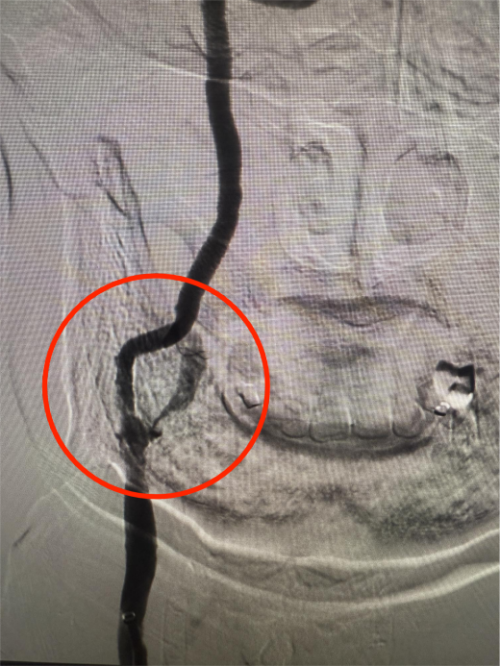

手术过程中,血管介入科团队以毫米级精度开展穿刺、置鞘、导引导管到位等步骤,精准地将微导丝穿过狭窄血管段,随后放置远端保护装置,如同为大脑血管筑牢“安全屏障”,有效预防术中斑块脱落引发栓塞。紧接着,选用合适规格的预扩张球囊对狭窄部位进行轻柔扩张,为支架植入开辟通路,随后将一枚自膨式支架精准送达狭窄段,缓慢释放并确认支架完全展开、贴壁良好。整个手术历时约60分钟,患者术后造影显示,患者颈内动脉狭窄部位血流完全恢复通畅,无残余狭窄,手术达到了团队预期的效果。

上图为手术过后血管狭窄明显改善,症状改善